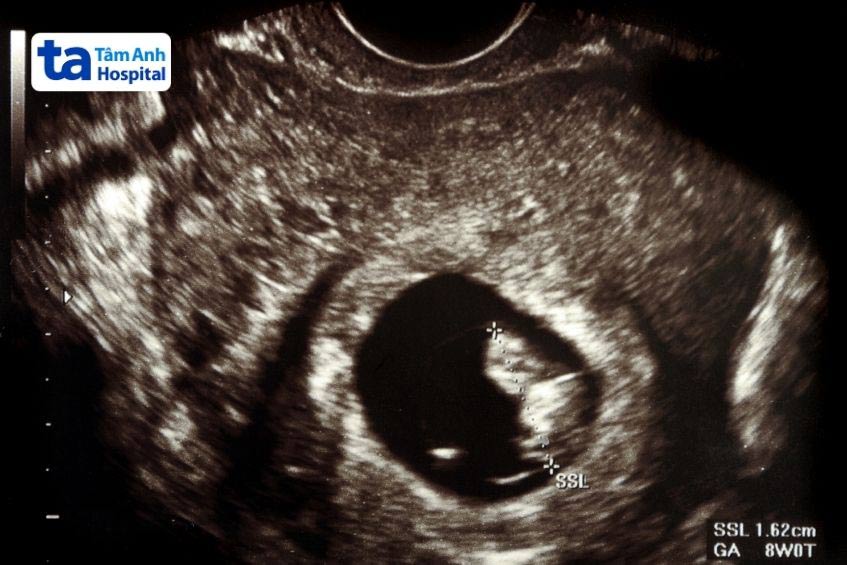

Thai tuần 9 kích thước bao nhiêu? Lúc này, kích thước của thai nhi có thể tương đương với một quả nho, dài khoảng 2.3cm từ đầu đến mông và nặng khoảng 20g. Mặc dù còn rất nhỏ nhưng thai nhi lúc này đã phát triển nhanh chóng và dần có hình dáng của cơ thể con người thu nhỏ.

Đầu thai nhi vẫn có kích thước lớn, chiếm khoảng một nửa kích thước cơ thể nhưng sẽ trở nên cân đối hơn trong các tuần tiếp theo. Các cơ quan nội tạng chính như tim, não, phổi, thận và ruột đã bắt đầu phát triển, xương cũng bắt đầu được hình thành. Các bộ phận khác như khớp vai, đầu gối, mắt cá chân, khuỷu tay cũng đã có thể chuyển động. (2)

Kích thước và hình dạng thai nhi ở tuần thai thứ 9 là những chỉ số quan trọng giúp các bác sĩ theo dõi, đánh giá sự phát triển của thai nhi. Trong trường hợp các chỉ số tăng trưởng của thai quá chậm hoặc quá nhanh có thể là dấu hiệu của những vấn đề sức khỏe đáng chú ý.